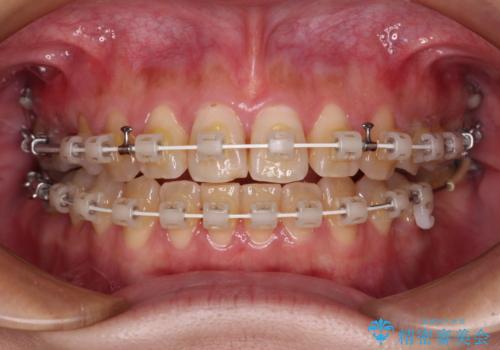

- 奥歯に問題が多くて困っているとのことで来院された患者様です。

開咬により奥歯のみが接触している状態で、前歯部にほとんど接触のない状態で、奥歯に非常に負担のかかる咬み合わせでした。

また、欠損や根管治療の必要な歯など、むし歯による問題も多く散見されました。

まずはむし歯の治療を行い、その後ワイヤー矯正にて咬み合わせを改善し、途中インプラント埋入を行い、矯正治療後に補綴治療を行うこととしました。